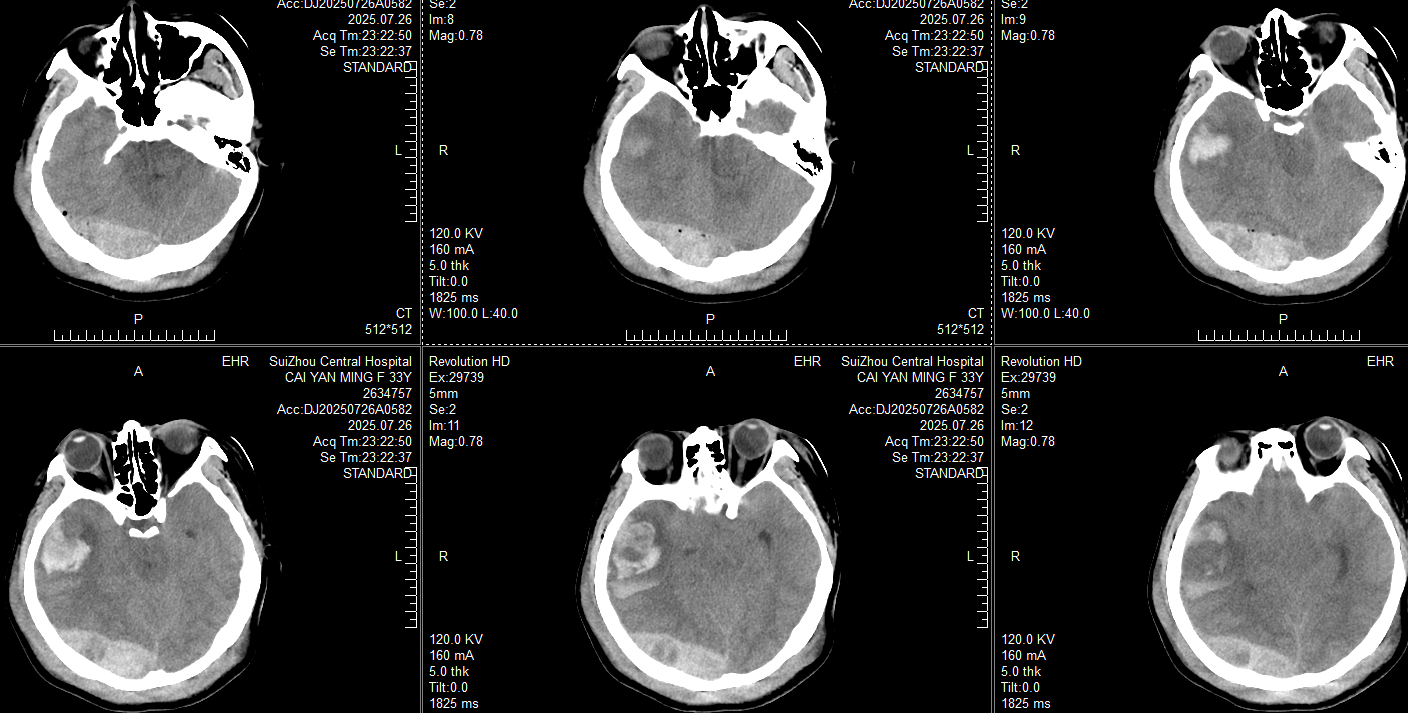

催促家属不能再犹豫,急诊开颅手术。设计左侧卧位,先做右枕部旁正中直切口清除硬膜外血肿,再做右侧额颞顶部去标准大骨瓣+右颞叶血肿清除术,体位和切口: